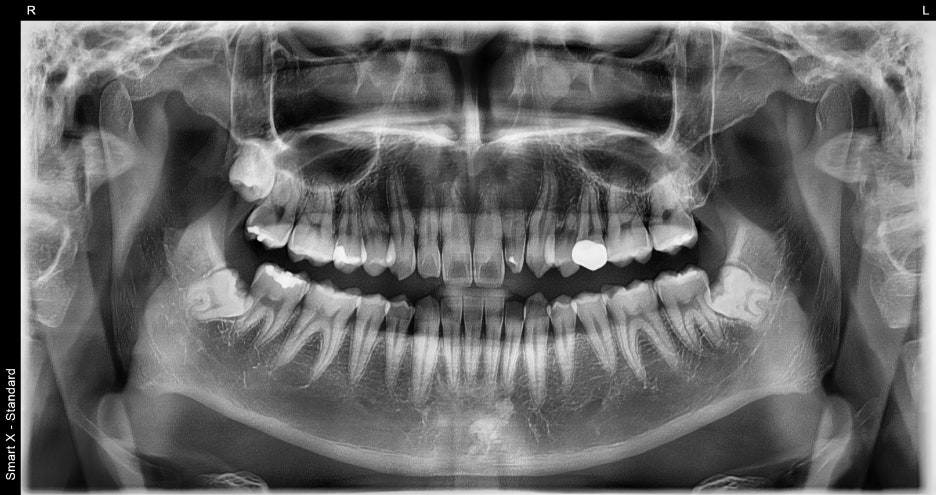

Initial condition of the patient

- Why was Object Zero needed in this case?

At the first visit, the patient was worried about these three issues:

Small lateral teeth next to the front teeth

Resin discoloration

Overall dark-looking tooth color

Although tooth size and shape vary from person to person,

if the balance on both sides differs greatly, it is difficult to achieve a natural look even by increasing brightness.